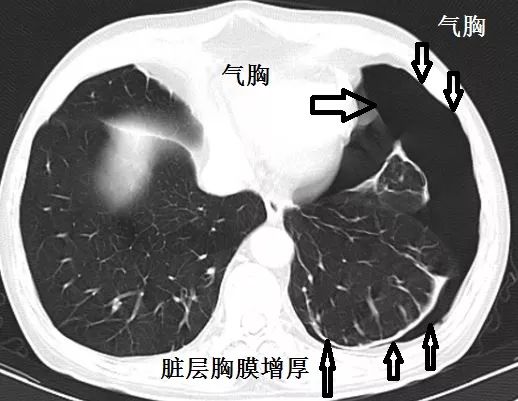

后来患者做了站立位胸片,结果显示:选择锁骨中线第二肋间穿刺抽气,是很不妥当的。

气胸主要在左下肺,左上肺的肺纹理清楚可见。

很明显,患者的气胸没有往高处走。贫穷限制了我们对奢侈生活的想象力,胸膜的粘连限制了气胸的流动性。

对于这个患者,既然锁骨中线第二肋间不适合胸腔穿刺,那么选择哪个位置呢?

结合CT,选择腋前线第五、六肋间穿刺抽气,更妥当。